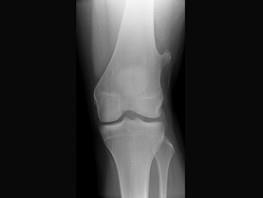

问题 患者,女性,39岁。发现左大腿下段后部有一包块,质较硬,无明显疼痛感觉,请结合所提供的图像,选择最佳选項 ( )

选项 A、骨软骨瘤 B、骨瘤 C、软骨瘤 D、骨肉瘤 E、软骨肉瘤

答案 A